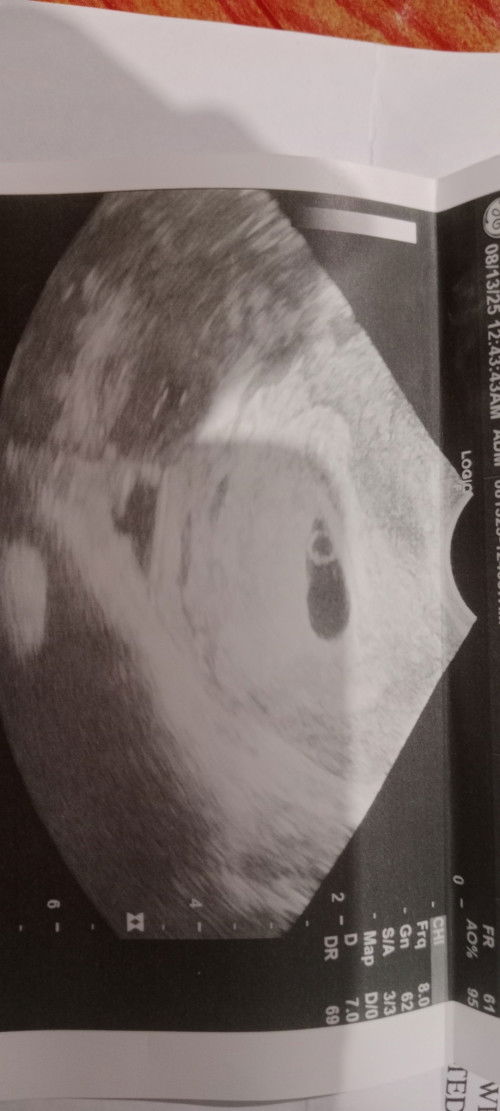

ᴍɢᴀ ᴍᴏᴍᴍɪᴇs ᴘᴏssɪʙʟᴇ ᴘᴏ ʙᴀ ɴᴀ ᴛᴡɪɴs ᴇᴛᴏ ᴍᴀsʏᴀᴅᴏ ᴘᴀ ᴋᴀsᴇ ᴍᴀᴀɢᴀ ᴇ 5 ᴡᴇᴇᴋs ᴀɴᴅ 1 ᴅᴀʏ ᴘᴀʟᴀɴɢ , ᴡᴀʟᴀ ᴋᴀsᴇ

ᴍɢᴀ ᴍᴏᴍᴍɪᴇs ᴘᴏssɪʙʟᴇ ᴘᴏ ʙᴀ ɴᴀ ᴛᴡɪɴs ᴇᴛᴏ ᴍᴀsʏᴀᴅᴏ ᴘᴀ ᴋᴀsᴇ ᴍᴀᴀɢᴀ ᴇ 5 ᴡᴇᴇᴋs ᴀɴᴅ 1 ᴅᴀʏ ᴘᴀʟᴀɴɢ , ᴡᴀʟᴀ ᴋᴀsᴇ ɴᴀᴋᴀʟᴀɢᴀʏ ɴᴀ sɪɴɢʟᴇ ʟɪᴠᴇ ɪɴᴛʀᴀᴜᴛᴇʀɪɴᴇ sᴀ ᴜʟᴛʀᴀsᴏᴜɴᴅ ᴋᴏ ɪғ ɪɪsᴀ ʟᴀɴɢ sʏᴀ sᴀʙɪ ʟᴀɴɢ ᴠᴇʀʏ ᴇᴀʀʟʏ ɪɴᴛʀᴀᴜᴛᴇʀɪɴᴇ ᴍᴀsʏᴀᴅᴏ ᴘᴀ ᴍᴀᴀɢᴀ